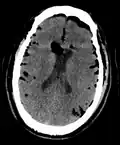

Large pneumocephaly secondary to surgical wound -

Pneumocephaly